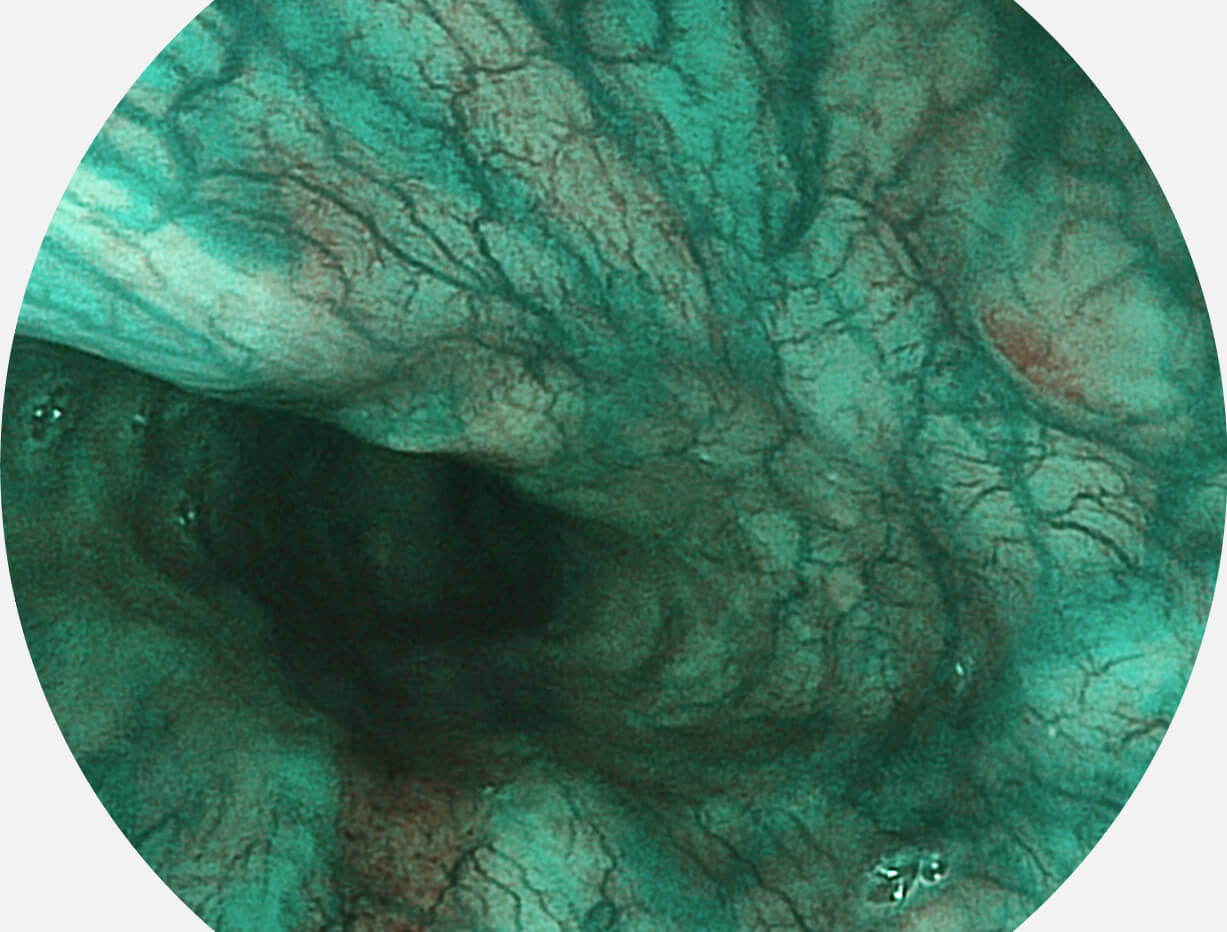

白光图像

SFI图像

Spectral Focused lmaging, SFI

图像具有高亮度、高黏膜血管颜色对比度的特点,且不改变粘液、食物残渣、粪便的基本颜色,可在中远景下进行观察,助力消化道早期疾病的诊断。